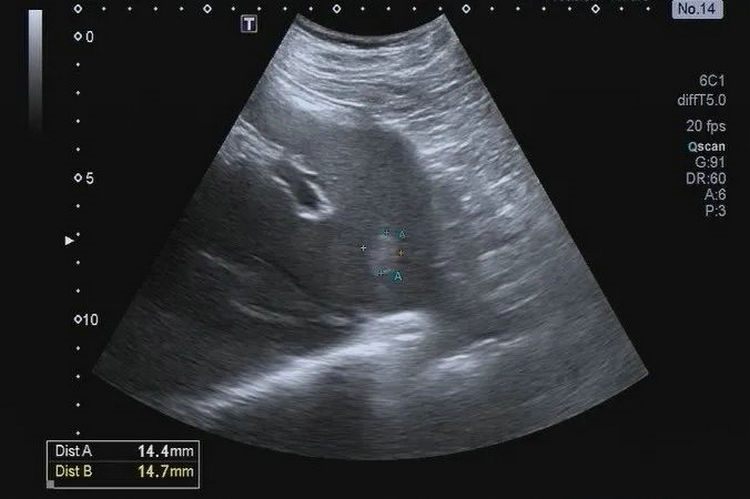

▲ 肝血管瘤

肝血管瘤目前常见的就是海绵状血管瘤,属于肝脏良性肿瘤,生长十分缓慢,通常每年生长速度小于2mm。需要提醒的是,超声体检检出的血管瘤只是筛查方法,不能作为定性诊断,对于第一次发现者,还需要结合其他的检查方法进一步明确诊断,例如超声造影等,而且,以后还需要定期进行复查。